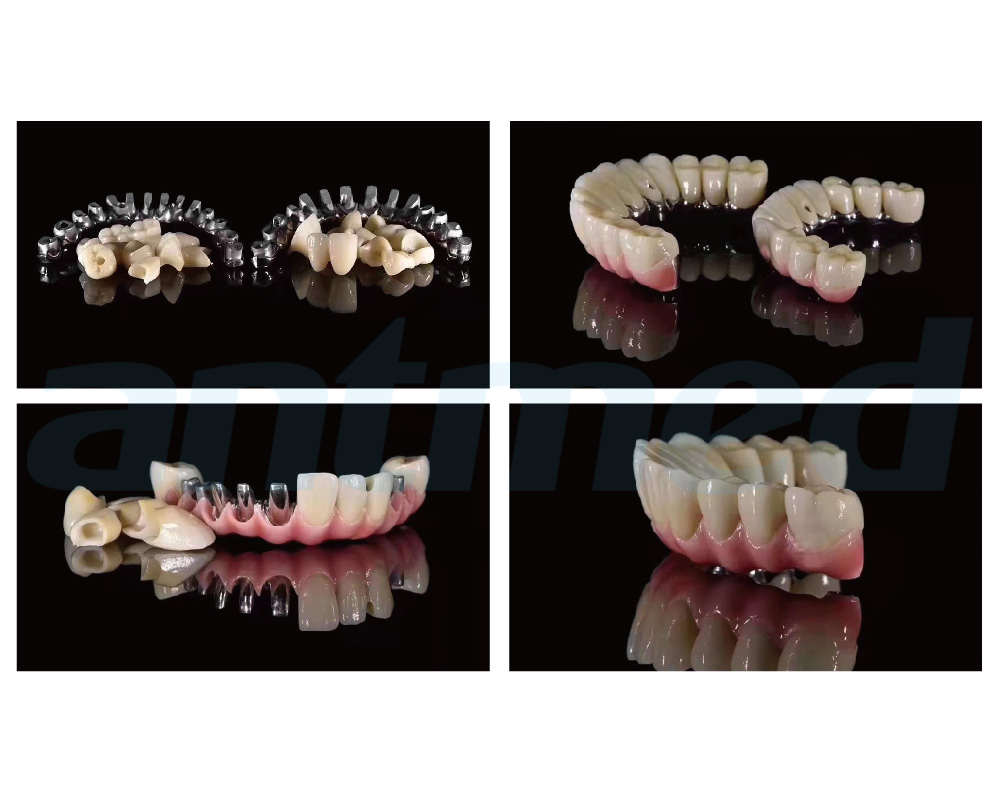

数字化种植修复类